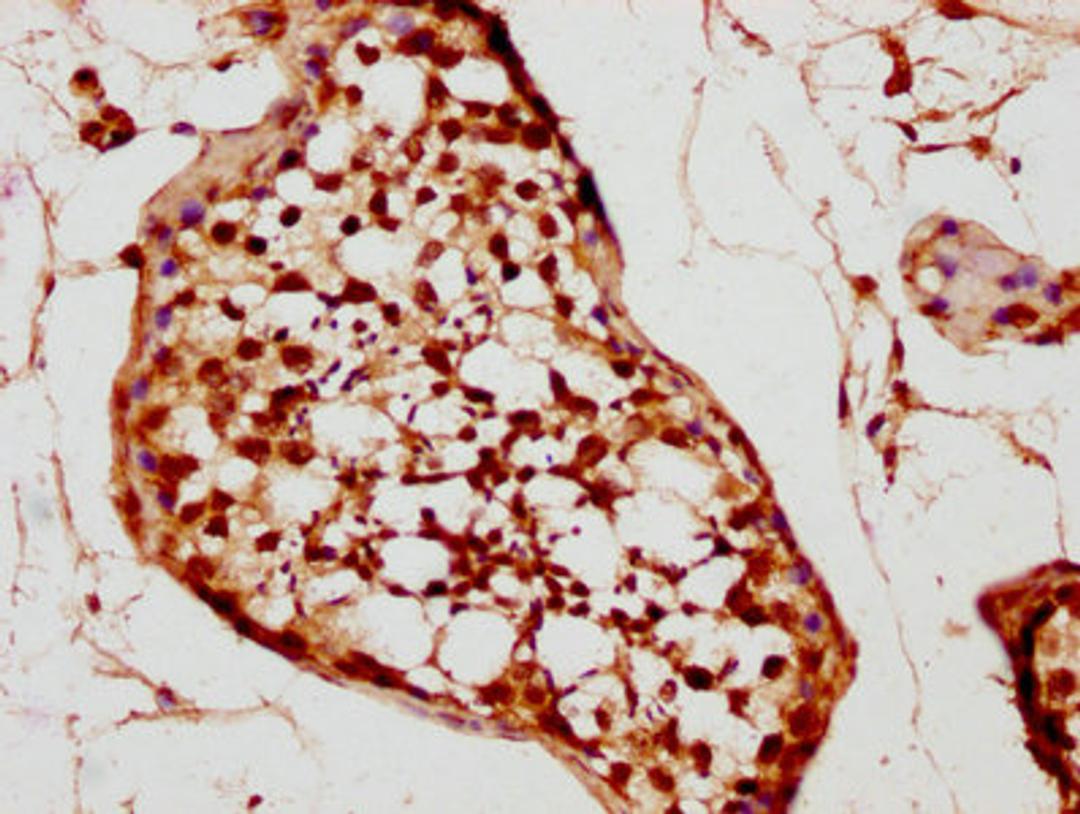

IHC image of CSB-PA024019LA01HU diluted at 1:200 and staining in paraffin-embedded human testis tissue performed on a Leica BondTM system. After dewaxing and hydration, antigen retrieval was mediated by high pressure in a citrate buffer (pH 6.0). Section was blocked with 10% normal goat serum 30min at RT. Then primary antibody (1% BSA) was incubated at 4°C overnight. The primary is detected by a biotinylated secondary antibody and visualized using an HRP conjugated SP system.